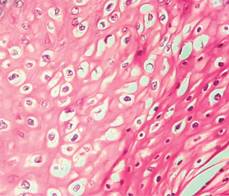

Se envían piezas a estudio histopatológico (Figura 3), identificando en cortes microscópicos patrón de crecimiento exofítico, con epitelio plano estratificado con acantosis importante. Las células basales con leve hipercromasia y atipia. La capa basal íntegra (Figura 4). En los tercios superficiales se identifican células con núcleos vesiculosos y citoplasma claro vascular (coilocitos) y escasas Figuras de mitosis (Figura 5). La capa superficial demuestra un leve incremento de láminas de queratina. El estroma fibroso con múltiples vasos congestivos. De acuerdo con estos hallazgos se establece el diagnóstico de enfermedad de Buschke-Lowenstein con lesión escamosa intraepitelial anal de bajo grado NIA 1. El paciente fue citado en consulta externa dos meses posteriores al procedimiento quirúrgico; la región perianal se encuentra con una adecuada cicatrización, sin evidencia de nuevas lesiones condilomatosas o presencia de fístulas (Figura 6).

Figura 5: En los tercios superficiales se identifican células con núcleos vesiculosos y citoplasma claro vascular (coilocitos) y escasas Figuras de mitosis.